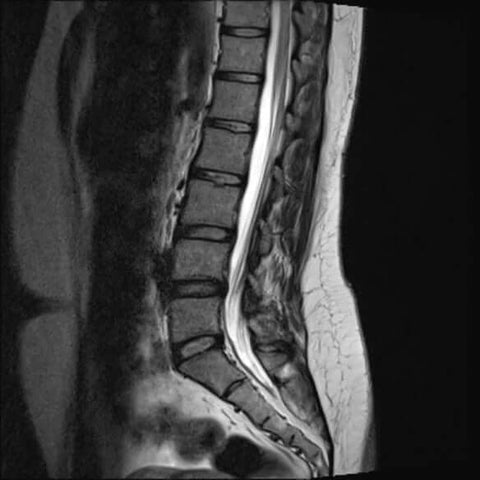

Hier sind die Röntgenaufnahmen der Lendenwirbelsäule einer Person mit Wirbelkompression.

Auf dem Bild links können wir sehen, wie die Wirbel einer Person auf Röntgenstrahlen aussehen, wenn sie zusammengedrückt sind. Auf dem Bild rechts sehen wir hingegen, wie die Wirbel richtig voneinander entfernt aussehen sollten.